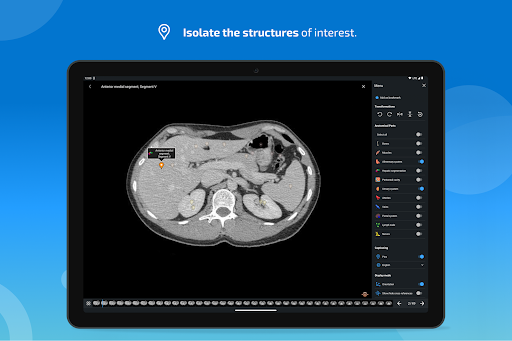

IMAIOS e-Anatomy es un atlas de anatomía humana para médicos, radiólogos, estudiantes de medicina y técnicos en radiología. Echa un vistazo a más de 26 000 imágenes médicas y anatómicas de forma gratuita antes de suscribirte a nuestro detallado atlas de anatomía humana.

e-Anatomy tiene más de 26 000 imágenes que contienen series de imágenes en vistas axiales, coronales y sagitales, así como radiografías, angiografías, imágenes de disección, gráficos anatómicos e ilustraciones. Todas las imágenes médicas fueron etiquetadas cuidadosamente, más de 967 000 etiquetas disponibles en 12 idiomas, incluida la Terminologia Anatomica latina.

- Desplácese por los conjuntos de imágenes arrastrando el dedo

- Acerque y aleje el zoom

- Toque las etiquetas para mostrar las estructuras anatómicas

- Seleccione las etiquetas anatómicas por categoría